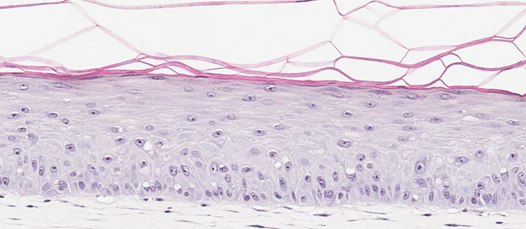

In-Vitro Organotypic Skin Culture (A)

Neonatal Skin Tissue (B)

Figure 2. Organotypic skin models have stratified epithelial morphology comparable to neonatal skin tissue. H&E staining of in vitro skin culture and ex vivo skin sections containing both dermal and epidermal stratified layers (A, B). Filaggrin staining identifies cornified keratinocyte layers (brown) (C, D).